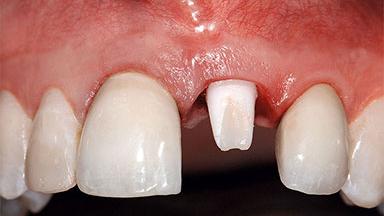

Replacement of a Missing Upper Left Central Incisor: Late Placement of an RC Bone Level Implant, CAD/CAM Zirconia Abutment

A healthy 37-year-old female patient was referred for a consultation on the replacement of missing tooth 21 with an implant-supported restoration. She stated that several years previously the tooth had been traumatically avulsed following a motor vehicle accident. The tooth was replaced with a three-unit fixed partial denture (FPD) immediately afterwards. Over time, she became disillusioned with the FPD and looked for a different option, including orthodontic therapy. She presented still in her orthodontic appliances, with the pontic sectioned free from the FPD but attached to the archwire. Her orthodontist felt that orthodontic treatment had been successfully completed, but nevertheless referred her before removing the appliances in case adjustments were necessary.

Abutment Type CAD/CAM